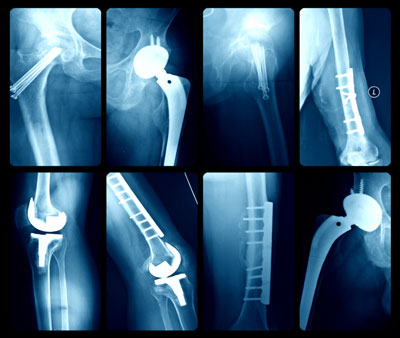

The implants are categorized by the U.S. Food and Drug Administration (FDA) as high-risk surgical devices, yet have been allowed into the marketplace without first going through clinical trials, where a product is tested to determine its safety and effectiveness. They failed at a dangerously high rate, often requiring reparative surgery at least four times as often as traditional hip replacement surgery.

U.S. hospitals perform 48 million medical procedures each year, according to the U.S. Centers for Disease Control and Prevention. Of that number, roughly 676,000 patients undergo total knee replacement surgeries and 327,000 undergo total hip replacement surgeries. While the commentary focuses on metal-on-metal hip implants, Redberg noted that there are many more devices that slip through the same FDA loopholes.